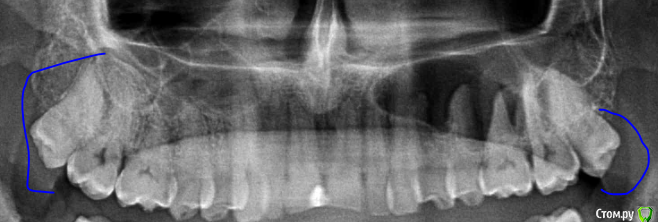

alex2016 Опубликовано 23 апреля, 2016 Поделиться Опубликовано 23 апреля, 2016 Добрый день, Сегодня был у стоматолога в профилактических целях. Т.к. нахожусь в США, то насчитали на ремонт 2600$ (учитывая страховку), т.к. 2600 тратить не сильно горю желанием хочу посоветоваться. Вопрос #1. В одном из зубов (его назвали №19 вроде как, снимок 1) врач обнаружил абсцесс. В этом зубе делали депульпирование и врач сказал, что депульпирование было сделано не до конца и на снимке это видно, т.е. они хотят заново вскрывать канал и заливать его (оба). К тому же он сказал, что в канале застрял кончик сверла (тут не уверен что это называется именно сверло) и его придётся доставать, возможно со стороны десны, если традиционным методом сделать это не получится. Абцесс он мне показал на снимке как небольшое затемнение на челюсти. Зуб не болит и кроме того, что между ним застряёт еда и он сам выглядит не презентабельно ничем не мешает, врач предлагает ставить коронку. Насчёт коронки возражений нету, т.к. еда застряёт и зуб выглядит не презентабельно, хотя в глаза это не бросается т.к. это моляр, а вот насчёт абсцесса я бы хотел уточнить здесь и получить второе мнение. Вопрос #2. Доктор предлагает поставить коронку на зубе #30, картинка #2. Хотя на зубе и достаточно большая пломба, он не выглядит не презентабельно и абсолютно не беспокоит, конечно, он выглядит чуть хуже обычного зуба, но гораздо лучше зуба #1. Сам я склоняюсь к тому, что пока с этим зубом делать ничег не нужно, но второе мнение хотелось бы всё-таки выслушать. Вопрос #3. Доктор предлагает удалить верхние зубы мудрости, т.к. они оказывают давление на дёсны или ещё куда-то там. Здесь я склоняюсь к тому, что он может быть прав насчёт верхнего зуба, потому что у меня там периодически застряёт еда между десной и самим зубом и вызывает неприятные ощущения, правый верхний зуб мудрости абсолютно никаких негативных ощущений не вызывает. Есть ли возможность избавиться от застрявания еды между зубом и десной (это происходит сзади-справа) без удаления зуба? Можно ли удалять один зуб мудрости, а не оба? Вопрос #4. У меня не правильный прикус из-за которого сточились передние верхние зубы, доктор предлагает удалить два верхних зуба, которые идут за клыками, подтянуть верхние передние зубы вперёд и поставить на них коронки, чтобы вернуть хороший прикус и эстетику (сейчас при закрытом рте расстояние между передними зубами верхней челюсти и нижней примерно в 1см). Вся эта процедура займёт кучу времени, т.к. придётся ставить брекет систему и удалять зубы. В клинике в Киеве мне тоже предлагали такой вариант. Зубы хочу сделать, чтобы улыбка стала красивее, поэтому вопросы: А. Обязательно ли удалять 2 зуба для этой процедуры?Б. Если удалить два верхних зуба мудрости, не отодвинутся ли зубы назад сами по себе?В. Хороший ли вариант ставить коронки на абсолютно здоровые, но немного сточенные зубы дли улучшения эстетики? Возможно зубы можно просто нарастить?Г. Не повлияет ли удаление двух зубов на положение верхней губы? При закрытом рте отклонений в прикусе особо не заметно. Благодарю за ответы. Ссылка на комментарий

DmitrySH Опубликовано 23 апреля, 2016 Поделиться Опубликовано 23 апреля, 2016 3 вопрос, скорее всего да, но не по снимку об этом рассуждать Ссылка на комментарий

alex2016 Опубликовано 23 апреля, 2016 Автор Поделиться Опубликовано 23 апреля, 2016 (изменено) Вопрос 1.Да, ревизия каналов нужна, коронка нужна, инструмента не увидел на снимке, самое интересное срезано.. нужен снимок еще как минимум 5 мм ниже.Вот сделал скриншот с другой фотографии. Качество какое есть, если нужно могу спросить нет ли у них качества получше, такое впечатление что отсканировали в самом плохом качестве, т.к. то что они мне показывали выглядело более детализировано. вопрос 2.Может быть не коронку, но керамический оверлей очень кстати, и вкладку или пломбу на 5ый зуб перед ним и 5ый над ним.Благодарю. Доктор, почему-то не упоминал об этой возможности, рассказывал только про импланты и коронки. Уточню насчёт этого. 3 вопрос, скорее всего да, но не по снимку об этом рассуждатьДа в плане того, что можно удалять только один зуб, или то, что можно избавиться от проблемы без удаления зуба? Зуб не болит абсолютно и я даже не знал о том, что это зуб мудрости, просто когда я ем орехи или морковку и они попадают между десной и зубом, то десна воспаляется и вызывает неприятные ощущения, вот сейчас абсолютно нормально и зуб не достаёт совсем, но когда доктор смотрел этот зуб я отчётливо понял, что это именно то место, потому что он его немного зацепил своим прибором, т.е. какая-то проблема там есть, но неужели такая мелочь решается только методом удаления зуба? Изменено 23 апреля, 2016 пользователем alex2016 Ссылка на комментарий

DmitrySH Опубликовано 23 апреля, 2016 Поделиться Опубликовано 23 апреля, 2016 По таком снимку тоже наличие/отсутствие инородного тела в канале сложно определить, но факт что требуется лечение.Ваши верхние восьмые зубы не используются по назначению. Можете смело удалять, в функциональном аспекте ничего не потеряете. 1 Ссылка на комментарий